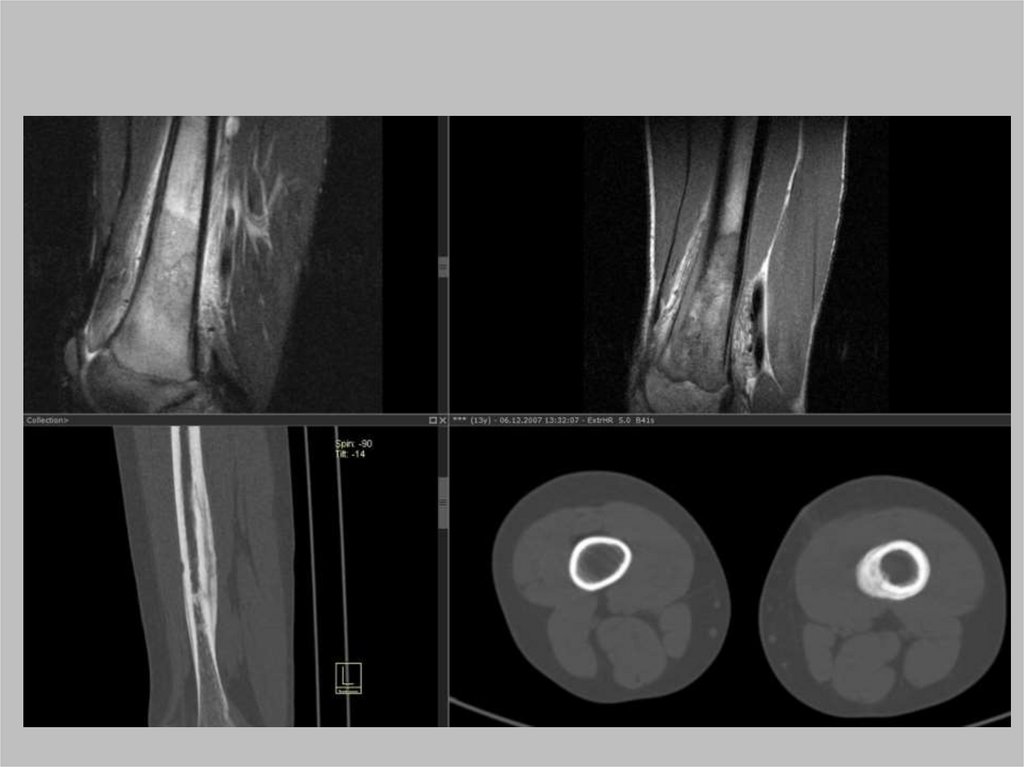

Костные опухоли в области

тазобедренного сустава